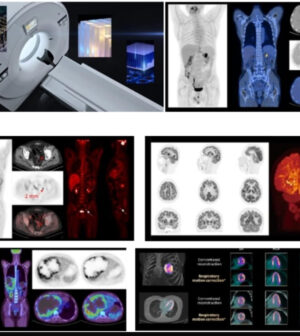

Medicina Futura potenzia la diagnostica con la PET/TAC di ultima generazione

Medicina Futura ha acquisito una PET/TAC di ultima generazione, una tecnologia avanzata che rivoluziona la diagnosi medica. Grazie alla sua superiore risoluzione spaziale, questo nuovo sistema garantisce una precisione diagnostica senza precedenti, permettendo di rilevare e monitorare patologie con maggiore accuratezza. L’integrazione dell’intelligenza artificiale consente di ridurre notevolmente i tempi d’esame e le dosi di radiazioni, migliorando significativamente la sicurezza e il comfort per i pazienti, in particolare per donne, giovani e soggetti più fragili, che traggono vantaggio da esami meno invasivi.

“Con questa innovazione, Medicina Futura migliora ulteriormente la qualità delle diagnosi, rispondendo, altresì, alle esigenze di un’assistenza sanitaria più rapida e maggiormente personalizzata. La nostra missione è continuare a garantire ai pazienti tecnologie all’avanguardia per un servizio sempre più efficace”, ha dichiarato Arturo Improta, fondatore di Medicina Futura. L’azienda è pronta a scrivere il futuro della diagnostica, mettendo al centro l’innovazione e la ricerca. Con l’introduzione di tecnologie avanzate e metodologie all’avanguardia, si prepara a offrire soluzioni diagnostiche sempre più precise ed efficaci. Inoltre, la struttura diventa un punto strategico dell’area nord di Napoli, un vero e proprio faro per la salute e il benessere della comunità, contribuendo al progresso del settore sanitario e rafforzando la posizione della zona come polo di eccellenza.